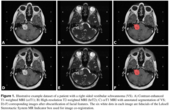

Segmentation of Vestibular Schwannoma from Magnetic Resonance Imaging: An Open Annotated Dataset and Baseline Algorithm